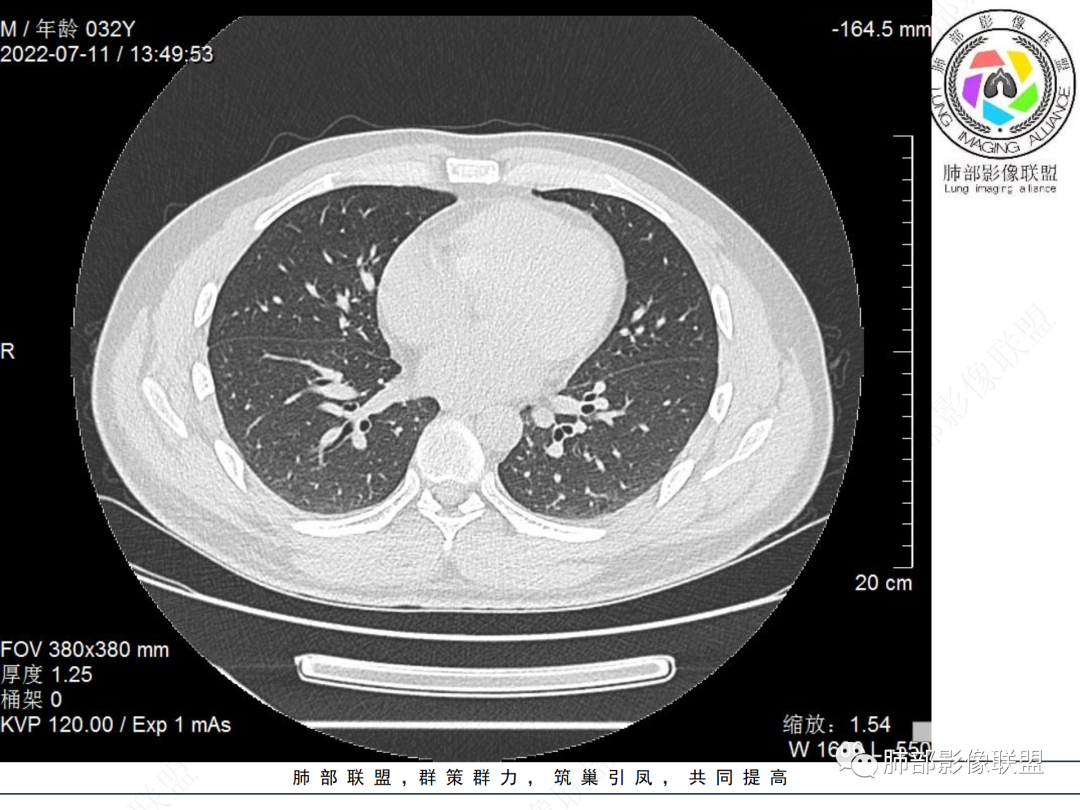

左肺下叶后基底段开口处结节,边缘光滑清楚,没有增强扫描,年轻男性患者痰血三天,考虑1.良性病变:腺瘤、错构瘤、平滑肌瘤

2.恶性:类癌、粘液表皮样癌。

左肺下叶外后基底段气管内见结节状影,边缘部分清晰。考虑错构瘤,待排恶性病变。

左肺下叶气管内外占位病变,咯血病史,考虑类癌,粘表待排。

青年男性,左肺下叶后基底段支气管开口软组织结节,边缘光整,气管镜提示质软,易出血,考虑类癌

左肺下叶后基底段开口处结节,边缘光滑清楚,年轻患者考虑鳞癌或腺样囊腺癌

左肺下叶气道腔内占位,远端无花花草草,疾病谱:鳞,类癌,粘表,腺样囊腺癌,小,无增强,不好判断,临床咯血,选类癌。

大支气管腔内结节,考虑类癌

左肺下叶后基底段开口处结节影,边缘光滑,患者年龄较小,首选类癌

男性,咳血左肺下叶支气管腔内结节影,没有阻塞性炎症,考虑类癌,鳞癌

年轻男性,支气管内结节,首先类癌

左肺下叶后基底段开口处腔内见壁结节,花生米样,宽基底,补充增强及矢状位重建,确定我无向壁外突破浸润生长,另见强化的特点,临床触之易出血,类Ca可能性大。

年轻男性,支气管腔内占位,边缘尚平整,年轻人,首先类癌,鉴别错构

年轻男性,咳血,左肺下叶后基底段支气管腔内结节,边缘光滑,首先考虑青年三件套,类癌大于粘液表皮样癌,支气管镜质软,触之易出血,鉴别血管瘤,平滑肌瘤

左肺下叶后基底段开口部结节,密度较均匀一致,边缘较光整,目测密度偏低,支气管镜示:质软、触之易出血,考虑恶性,类癌。

支气管腔内结节,有蒂与支气管壁连接,考虑良性病变可能性大,支气管错构瘤  血管瘤一类的

左肺下叶后基底段支气管腔内结节,有蒂,容易出血,先考虑良性病变,肉芽组织型血管瘤,与类癌鉴别。

青年男性,左肺下叶后基底段支气管开口软组织结节,边缘光整,气管镜提示质软,易出血,考虑恶性类癌

左肺下叶后基底段开口处结节影,边缘光整,年轻患者,伴咯血,考虑鳞癌,类癌不能排除